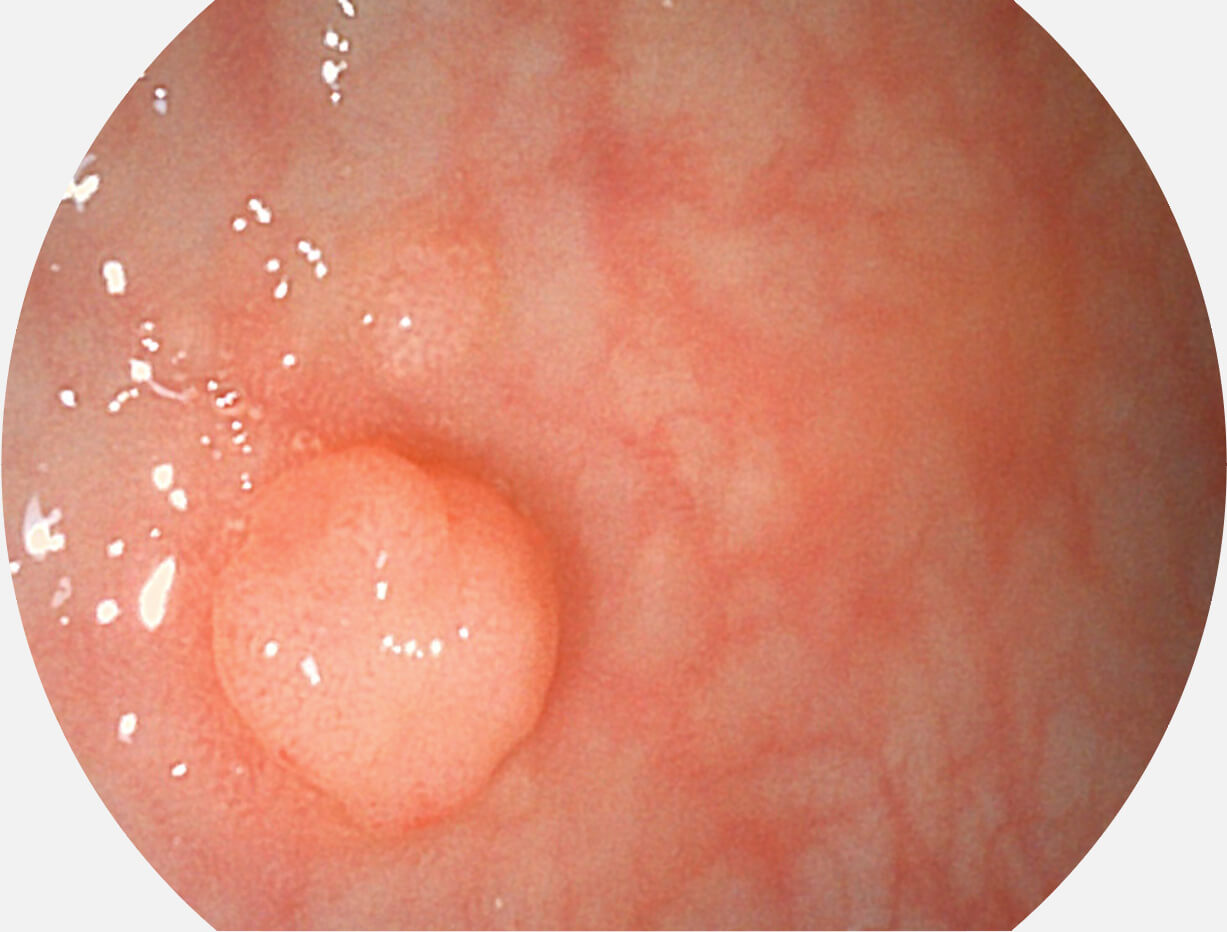

Versatile Intelligent Staining Technology, VIST

强调浅层黏膜结构的同时,保证照明亮度和提升浅层微血管与中层血管颜色对比度,病变边界更清晰。

白光图像